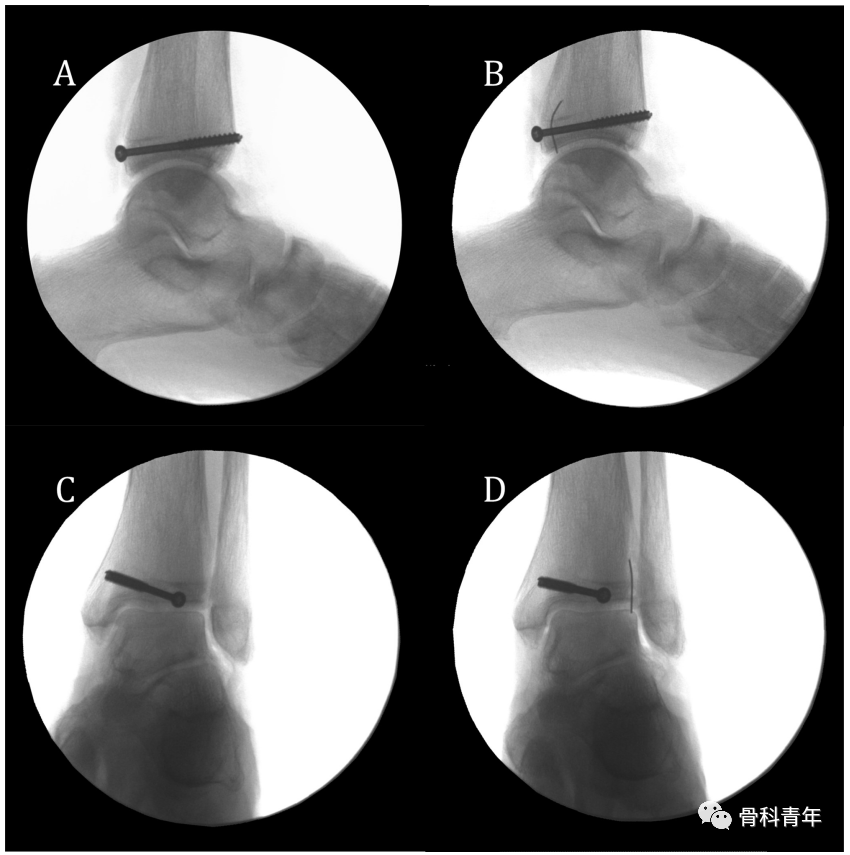

依上述研究结果,在如下的后踝钢板固定中,透视钢板部分位于PVSL线外侧,有影响下胫腓风险,因此将钢板内移至PVSL线内。

▲ 图中白色虚线即为PVSL线。